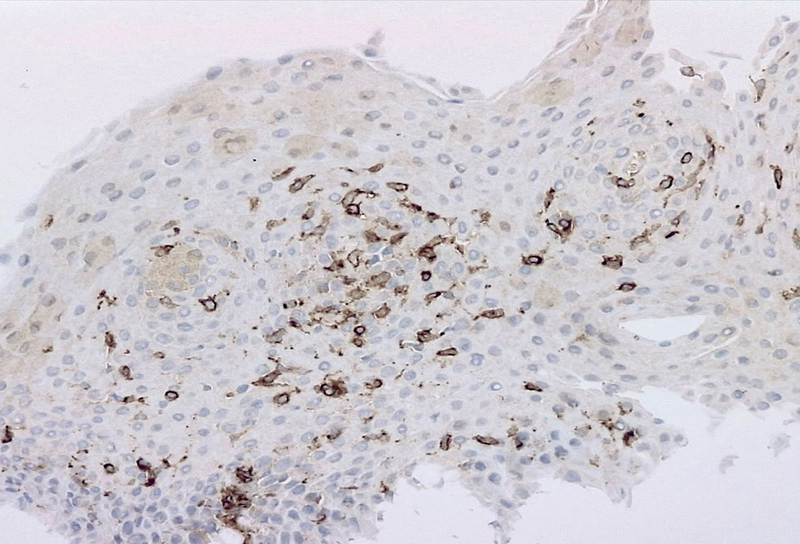

Microscopic examination revealed oesophageal squamous mucosa with an increased number of intraepithelial lymphocytes predominantly clustered around papillae, rare to absent granulocytes, intercellular oedema known as spongiosis and basal cell hyperplasia (Panels A and B). Most of the lymphocytes in the infiltrate were T cells CD3+ (Panel C). CD20 stain shows rare B cells (Panel D). CD4+ T cells outnumber CD8+ T cells (Panels E and F).

There is no standard number of intraepithelial lymphocytes required for diagnosis and studies have included various cut-off values, ranging from 20 to 50 lymphocytes/HPF.  A recently published consensus recommendation by an international expert panel suggests 40 lymphocytes per HPF as cut-off value, following Rubio’s initial criteria for diagnosis. Lymphocytic oesophagitis varies in the prevalence of CD4+ or CD8+ T cells. The predominance of CD4+ intraepithelial lymphocytes appears to be associated with dysphagia, primary oesophageal motility abnormalities and prominent spongiosis.